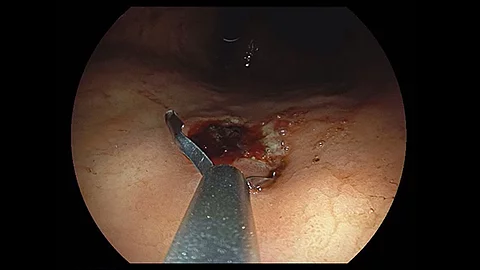

Endoskopisches LehrvideoKomplikation bei transgastraler Nekrosektomie

Im neuen Video zeigt Ihnen Prof. Dr. Jochen Weigt aus Magdeburg den Fall eines männlichen Patienten, der sich mit transgastraler Nekrosektomie bei akuter Pankreatitis in der Notaufnahme vorstellte. Welche Komplikation auftrat und wie die Therapie aussah, sehen Sie im Video.